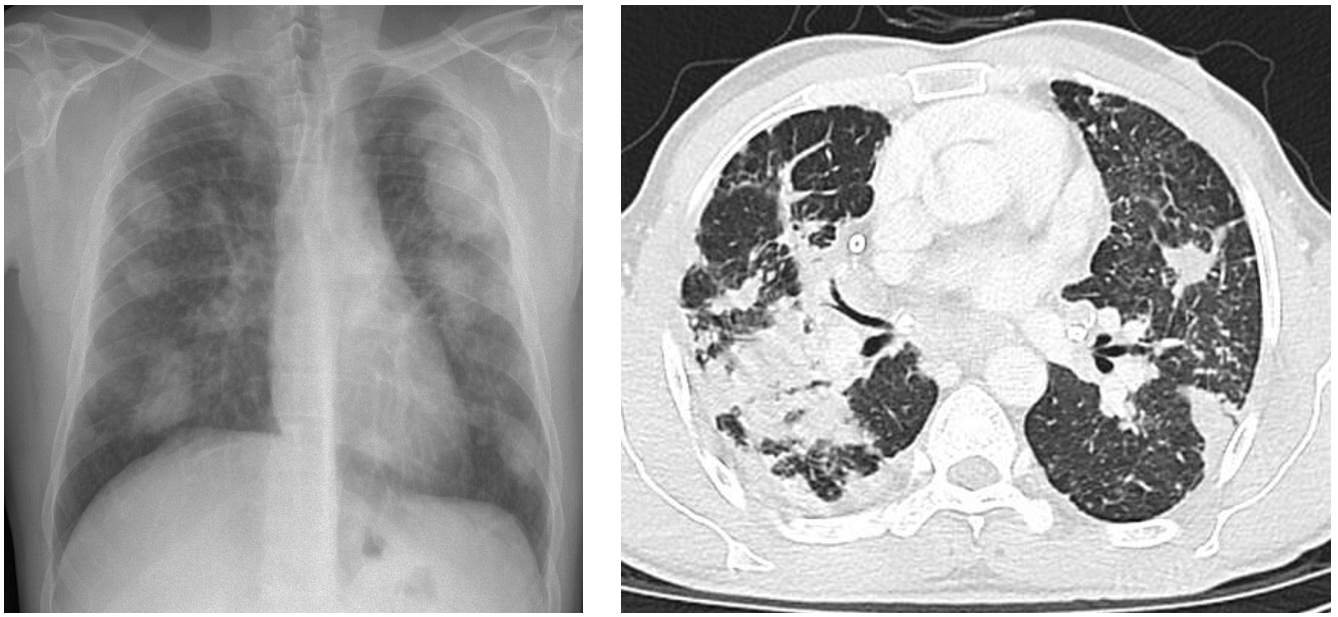

(1) CXR/CT

① 석면폐증: 폐하부 diffuse GGO, sagging heart, reticular opacities, subpleural line 등

(2) 임상양상 및 검사소견: 만성 규폐증과 유사

① 단순 CWP: 다수의 < 10 mm 크기의 nodule

② PMF: ≥ 10 mm 크기의 nodule